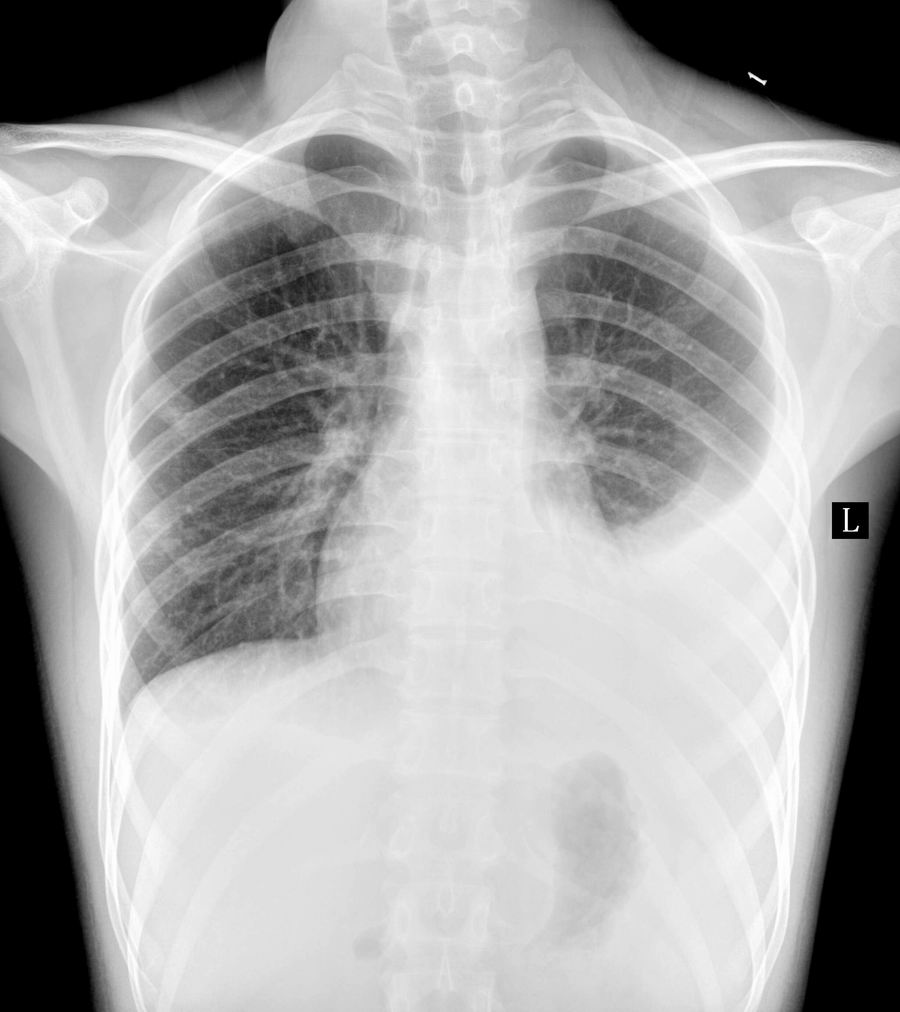

以下是引用一生何求在2010-5-12 9:35:00的发言:[br]两次片子对比可见左侧胸腔积液量有所减少,而右侧则增多;右肺小病灶考虑为一个比较稳定的病灶,有向纤维化或钙化方向发展的趋势 最终转变为陈旧性病变。[br]建议随诊复查。

以下是引用zhanggenliang在2010-5-12 16:49:00的发言:[br]右肺的高密度影应该是中叶吧。请问治疗过程。是抽水呢?还是抗结核治疗,还是抗炎。如果抽水应该化验,因为化验鉴别明了,如果抗结核就不用说了。如果是考大家,只能说影像较支持结核